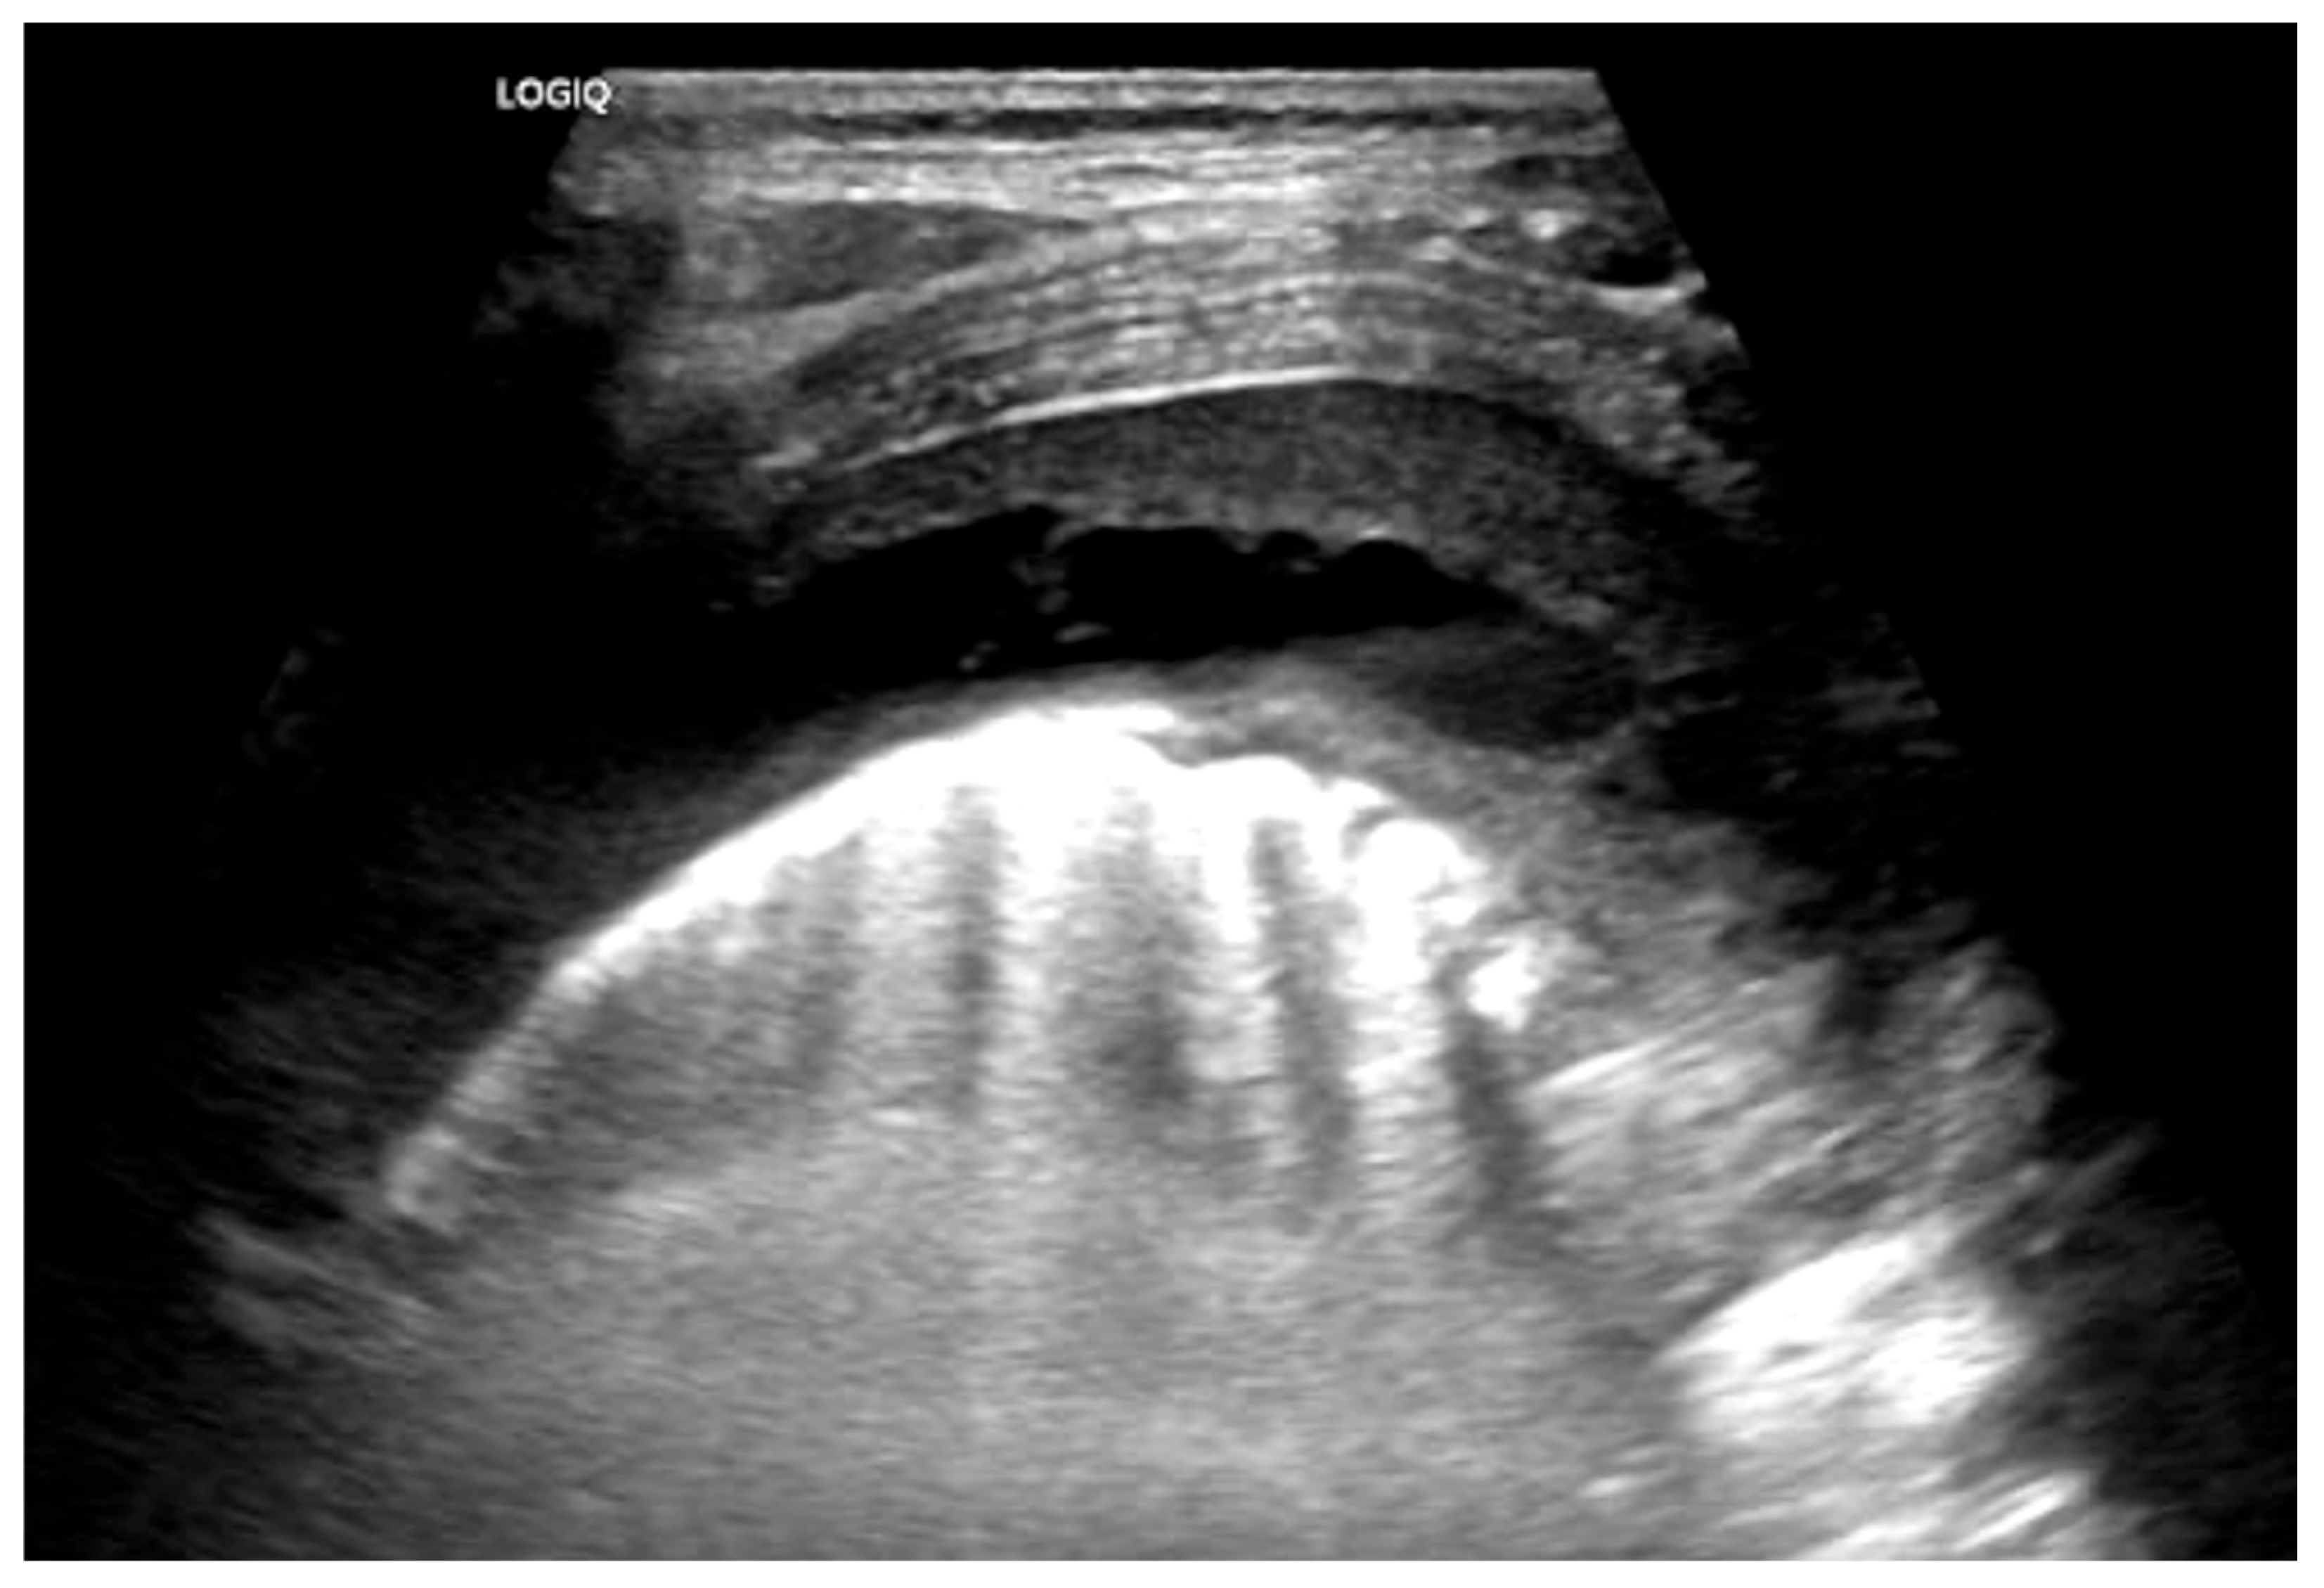

- Huang, W.E.; Matifoll, J.A.; Lord, D.; Haggie, S. A review of imaging in the diagnosis and management of complicated paediatric pneumonia. Paediatr. Respir. Rev. 2025, 54, 12–18. [Google Scholar] [CrossRef]

- Carrard, J.; Bacher, S.; Rochat-Guignard, I.; Knebel, J.-F.; Alamo, L.; Meuwly, J.-Y.; Tenisch, E. Necrotizing pneumonia in children: Chest computed tomography vs. lung ultrasound. Front. Pediatr. 2022, 10, 898402. [Google Scholar] [CrossRef]

- Kurian, J.; Levin, T.L.; Han, B.K.; Taragin, B.H.; Weinstein, S. Comparison of ultrasound and CT in the evaluation of pneumonia complicated by parapneumonic effusion in children. Am. J. Roentgenol. 2009, 193, 1648–1654. [Google Scholar] [CrossRef] [PubMed]

- Lai, S.-H.; Wong, K.-S.; Liao, S.-L. Value of lung ultrasonography in the diagnosis and outcome prediction of pediatric community-acquired pneumonia with necrotizing change. PLoS ONE 2015, 10, e0130082. [Google Scholar] [CrossRef]